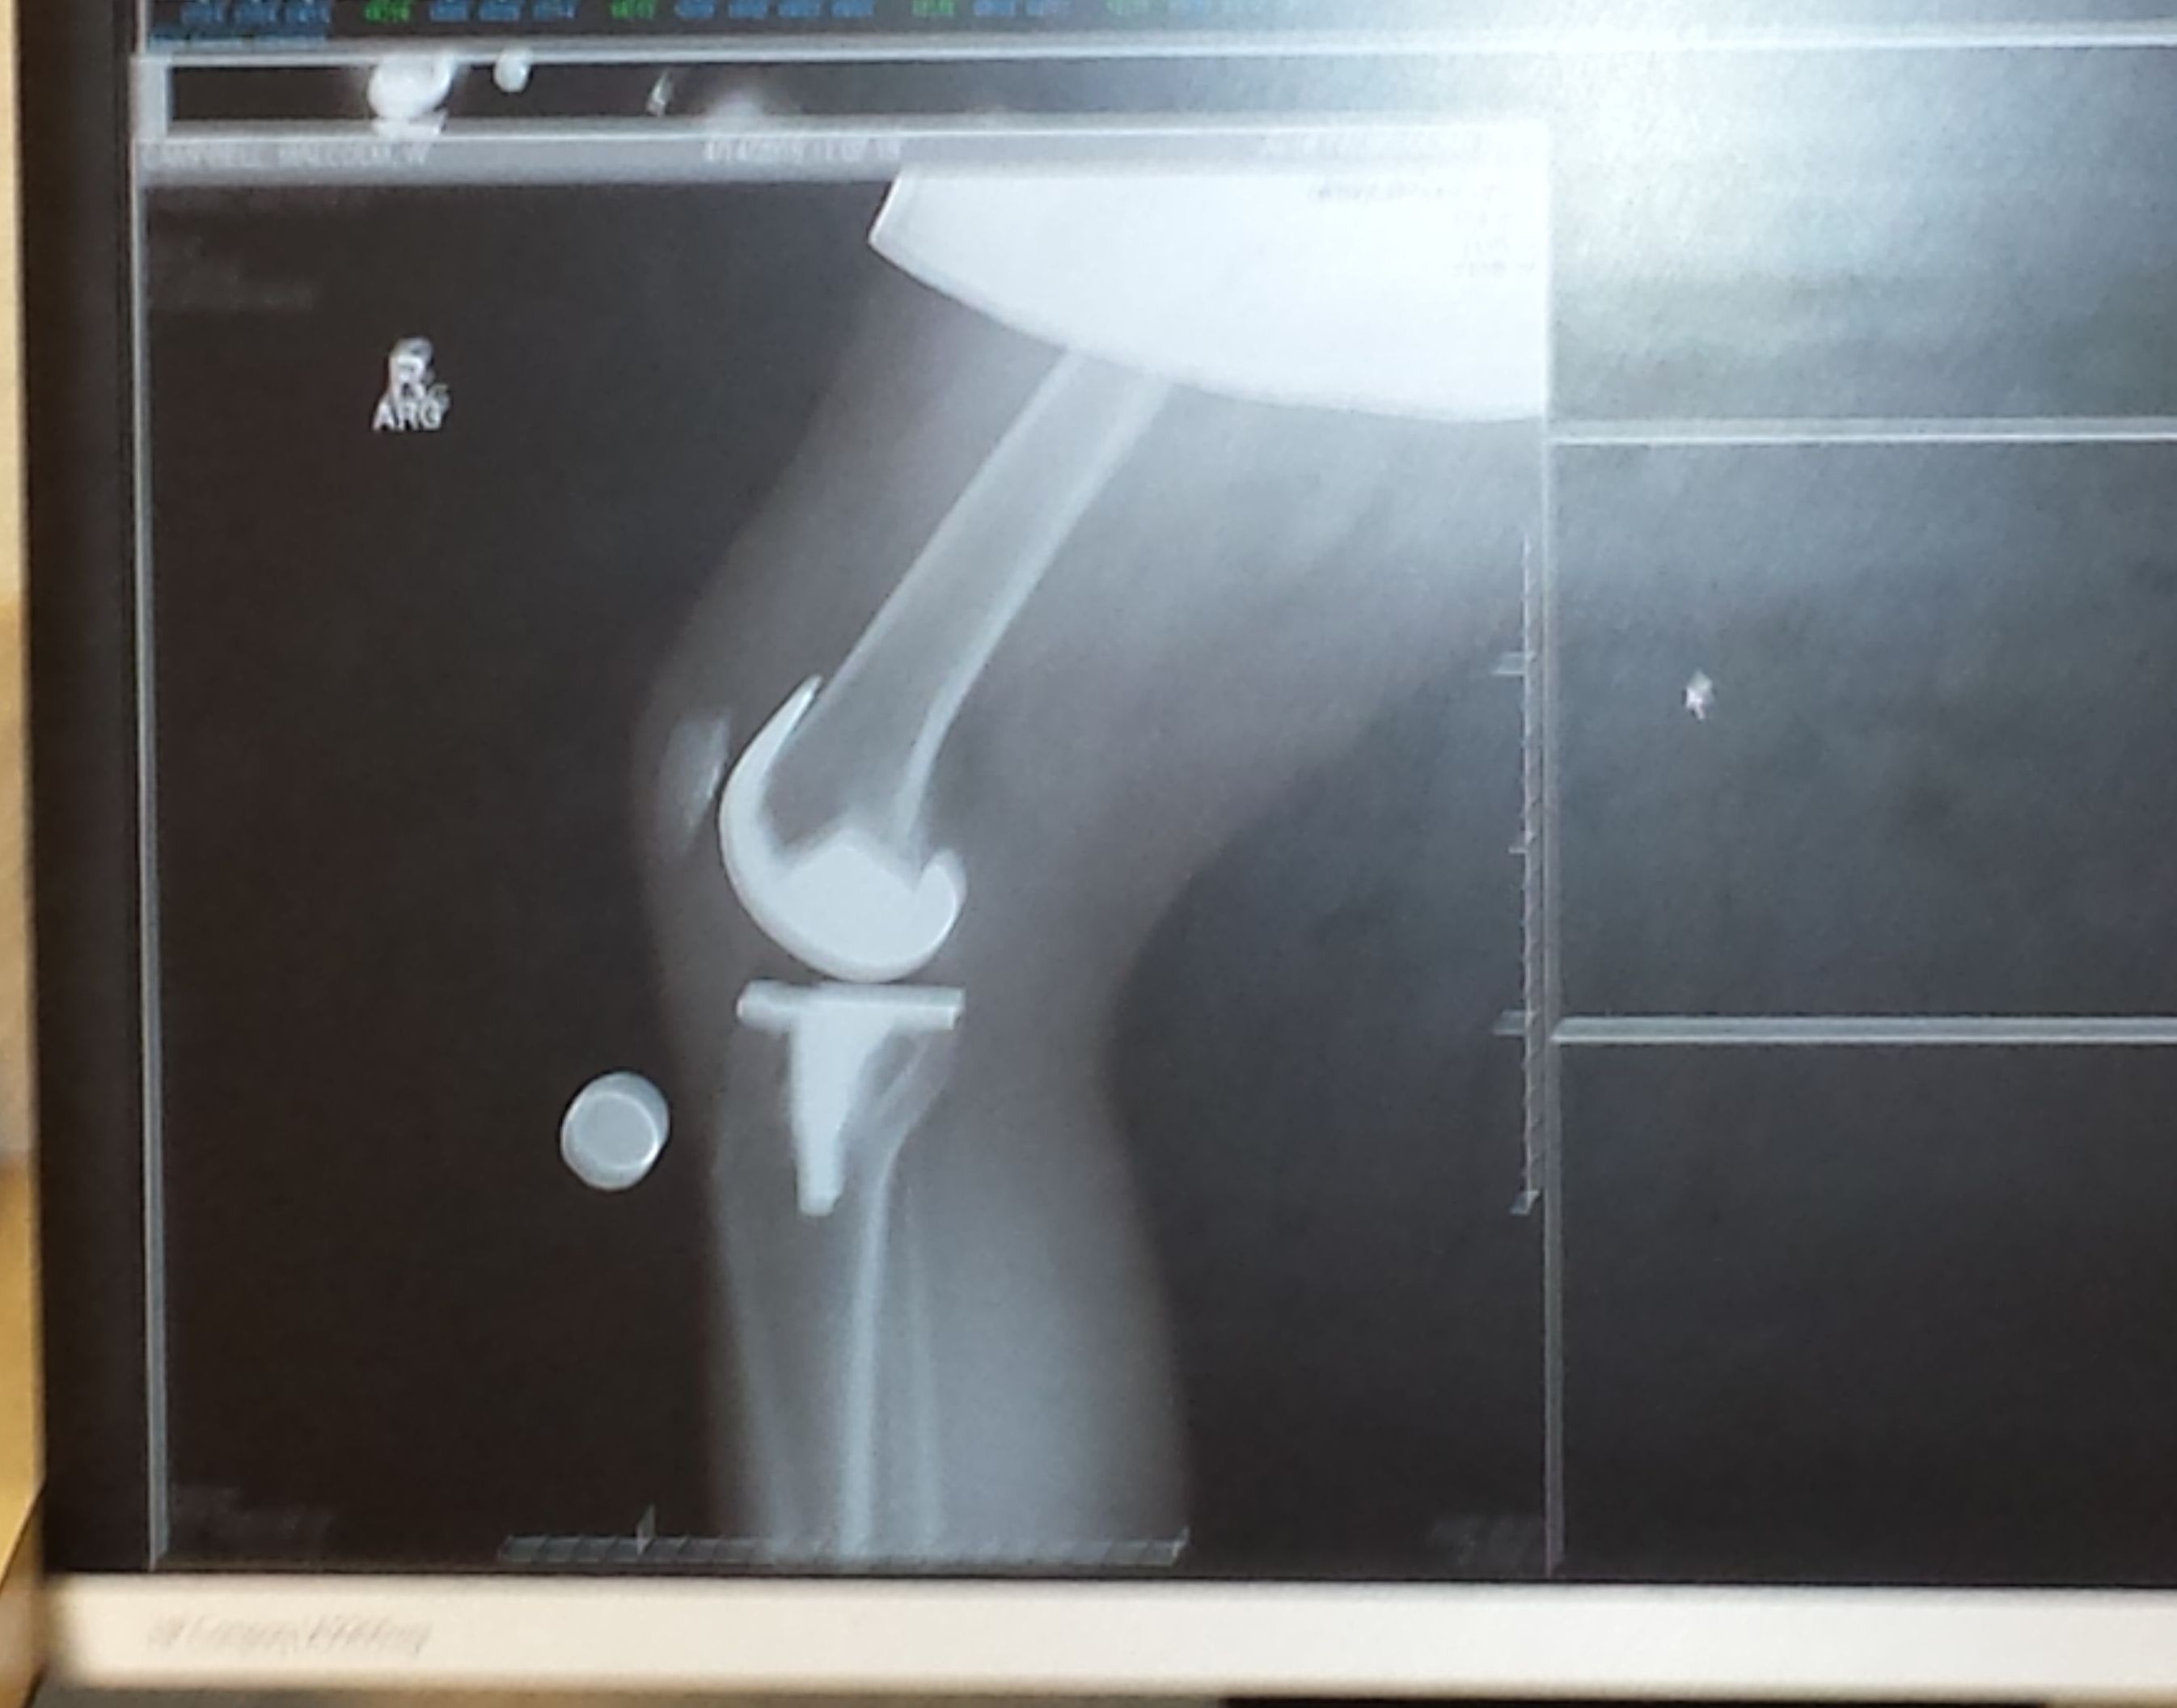

This summer, I had the distinct pleasure of having both of my knees opened up — they were last closed in 2015 and 2016 when an ortho replaced the right, then left knee. The procedure involved removing an old plastic “cushion” between the prosthetic joints and reinserting a new one. Sixteen days out from surgery, I took my first foray back into the woods for a 2.5-mile hike. While it wasn’t “easy,” it was the first step in recuperating so I can be back on the AT with a backpack in another four weeks.

Here’s what’s amazing: I went through the first “cushions” in about 4,000 miles. In essence, I’d worn out the “tread” on my tires. That’s 10 years and thousands of miles covered in the woods and on neighborhood walks. When I complete that cycle again, all I’ll need is new tires. Isn’t that something? That knees can be replaced, re-tread, and then sent back out for no-limits hiking, backpacking, skiing?

When I set out to hike the Appalachian Trail three years ago – 150 to 200 miles at a time – I earned the trail name “New Knees” because of the Uber cool scars on my legs. With even less-sightly, cooler scars, I look forward to a revised trail name: “New and Improved New Knees.”

After both knee replacement surgeries, I returned to consciousness with a yellow tag on my wrist labeled “Fall Risk.” Fair enough. I was wobbly and anesthetized. But to this day, friends and family joke that I need to wear that tag before any activity, including getting out of bed, brushing my teeth, and teaching, to name three.

From the first ascent of five steps over a stile to the campsite I reached around mid-afternoon, I felt good despite more than six hours of hiking. At first, I had the site to myself; however, an hour later, “Gunn Slinger” — Curtis Gunn, a professional cyclist — arrived and set up camp 15 yards away. He encouraged me to adopt a trail name, a practice I thought reserved for thru-hikers. With some hesitation, I dubbed myself “New Knees” for the right and left knee replacements hammered into place in 2015 and 2016. Gunn Slinger commented that he was happy to be present for my christening. We spoke a bit but mostly allowed one another to enjoy the experience.